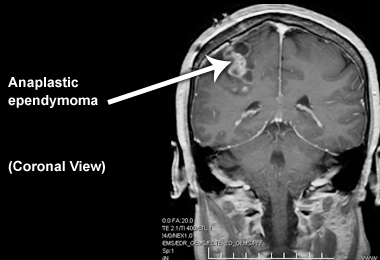

Coronal image

Below is an image of anaplastic ependymoma in an adult patient from the coronal view: